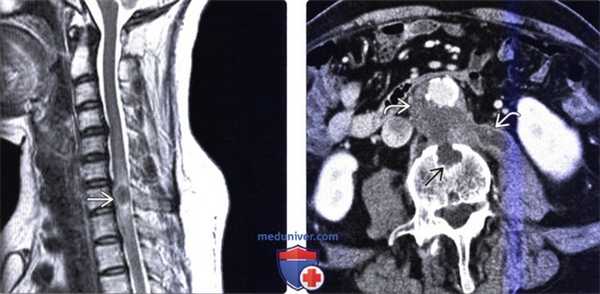

(Слева) Сагиттальный срез, Т2-ВИ: увеличение объема спинного мозга с гиперинтенсивностью сигнала его паренхимы. Изменения сигнала распространяются от уровня С2 до верхнегрудного отдела позвоночника. Пациент длительное время принимал глюкокортикоиды по поводу артрита, на фоне чего развился абсцесс спинного мозга, вызванный Listeria, и листериозный менингит.

(Справа) Сагиттальный срез, Т1-ВИ с КУ: гипоинтенсивность сигнала и увеличение объема спинного мозга с гетерогенным контрастированием паренхимы спинного мозга и контрастным усилением сигнала мягких мозговых оболочек. Такая картина является проявлением абсцесса спинного мозга и менингита, вызванных Listeria.